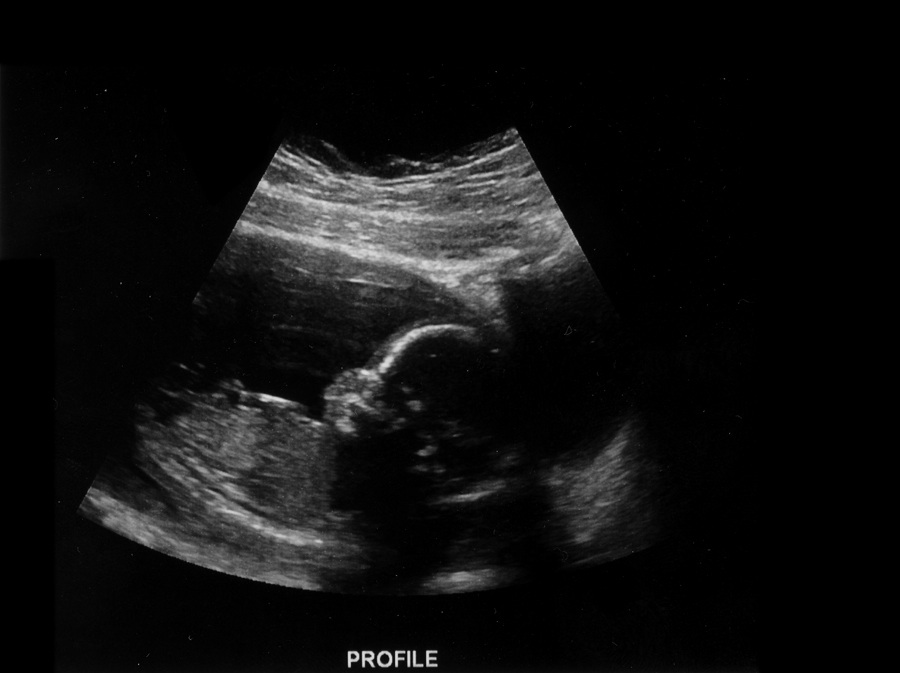

The tech couldn't tell us anything so we are still praying for healthy normal results but she did tell us that we are team BLUE! DH and I just cried we are so happy, although even if she said girl we would have still cried but it feels so remarkably real now! He was putting his arm over his face like he was trying to say "no more pictures" lol it was to cute and we saw him yawn and move around ugh so freakin cute. Almost half way to meeting my little man. I love him so much. To bad he couldn't stay still we got all the measurements but the pictures weren't that great but oh well I'm just praying the baby's results come back healthy.

Health update: Well the nurse just called and she said nothing came back abnormal and all his organs and sizes were what they wanted but they couldn't get a clear picture of his heart chambers so my OB wants the A/S repeated in 2-4 weeks. I know she said not to worry and I know my little man was being difficult but I can't help but be a little concerned. I'm thankful for the normal results today and just praying that the second scan comes out well too.